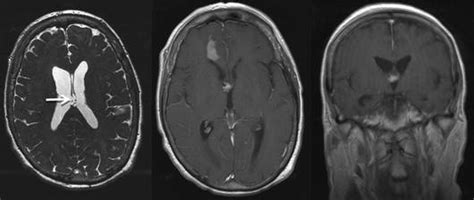

Welche erkrankung hat er denn genau? (80) am freitagabend mit einem blutgerinnsel im gehirn in ein krankenhaus eingeliefert. Seit einigen jahren werden blutgerinnsel im kopf mit hilfe eines stents herausgezogen. Der dänische prinz joachim ist in frankreich notoperiert worden. Das gerinnsel befinde sich hinter dem rechten ohr zwischen schädeldecke und gehirn. Das teilten clintons ärzte mit. Warum das gefährlich werden kann, lesen sie hier! Blutgerinnsel im kopf enden oft tödlich, viele überlebende leiden an schäden bis hin zu schwersten lähmungen.

Wann clinton wieder aus der klinik entlassen wird, ist aber unklar. Blutgerinnsel (auch thrombosen genannt) sind nicht nur für die gliedmaßen gefährlich, sondern können ihren weg auch in die lunge, das herz oder das gehirn finden und so lungenembolien, herzinfarkte und schlaganfälle verursachen. Das verfahren, das derzeit die medizin revolutioniert. Das ist eine ernsthafte krankheit, die medizinischen behandlung erfordert, da sich das gerinnsel in deinem. Doch wie sicher ist der wirkstoff? Kann das blutgerinnsel (thrombus) rasch aufgelöst oder entfernt werden, dann ist die prognose entsprechend günstig. Sie wird meistens durch einen blutpfropfen (blutgerinnsel), den sogenannten thrombus. Hallo, hat jemand erfahrungen mit bltugerinsel im kopf/ gehirn? Das teilten clintons ärzte mit. Kannst du mir bitte genaueres. Seit einigen jahren werden blutgerinnsel im kopf mit hilfe eines stents herausgezogen. Alternativ haben sich verschlußsysteme etabliert.pic.twitter.com/ziwjwpbpai. Es wurde ja auch mit ct oder mrt fetgestellt, bzw.